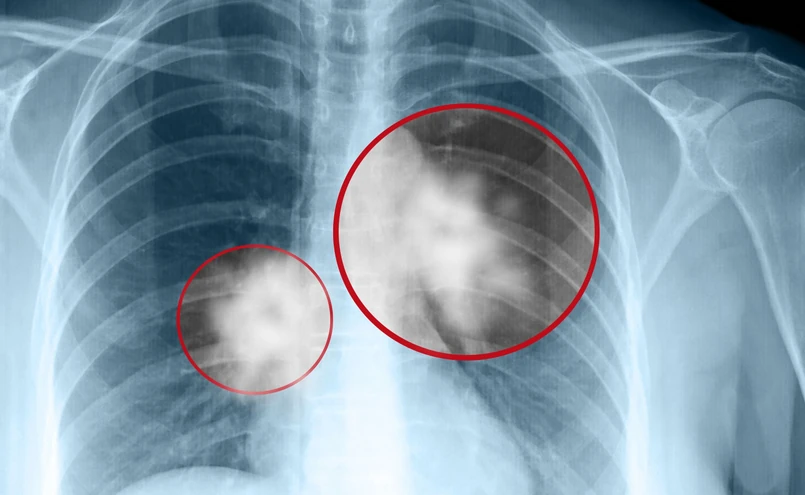

Jedynym badaniem pozwalającym wykryć raka płuca na wczesnym etapie jest niskodawkowa tomografia komputerowa (bez konieczności podawania kontrastu). „Wszystkie pozostałe badania, które wydawały się być pomocne w wykryciu wczesnego raka płuca, np. zdjęcie rentgenowskie czy analiza plwociny, okazały się wysoce nieskuteczne” – wyjaśnia prof. Ramlau.